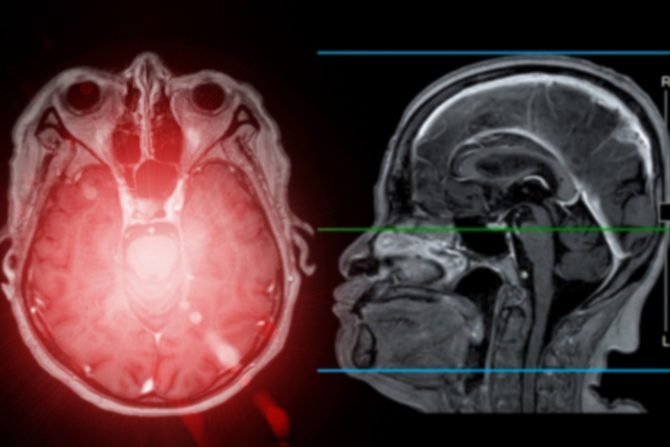

Dr de Havenon objašnjava da magnetna rezonanca koje se uradi u roku od 24 sata od početka simptoma moždanog udara može da obezbedi dosta bitnih informacija o neurovaskularnim problemima. Magnetna rezonanca može da otkrije potpuni moždani udar i pokaže povredu mozga, dok TIA ne izaziva oštećenja koja će biti vidljiva. Kompjuterizovana tomografija (CT) može da pomogne lekarima da isključe neka druga stanja i omogući snimanje mozga ako magnetna rezonanca nije dostupna.